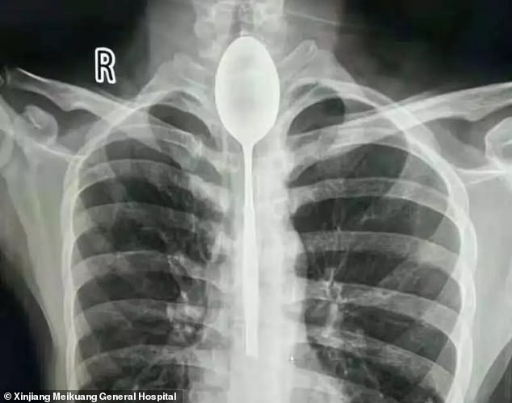

26-летний житель Синьцзяна целый год прожил с металлической столовой ложкой в животе, передает Life.ru

Как сообщает Daily Mail, китайские врачи были ошарашены, увидев рентгеновский снимок пациента. Изначально мужчина жаловался на боли в животе и затруднённое дыхание. Но, увидев снимок, он не удивился и объяснил, что проглотил ложку ещё год назад.

По словам молодого человека, он хотел удивить собутыльников трюком — проглотить столовую ложку и вытянуть её назад за верёвочку. Но что-то пошло не так — верёвка оборвалась, а ложка осталась внутри. Впрочем, по словам пациента, столовый прибор не мешал ему жить, поэтому он целый год не мог дойти до врачей.

Медики решили обойтись без полостной операции и вытащили ложку через рот, пока пациент находился под наркозом. К сожалению, за год мужчина всё-таки получил травму пищевода и теперь проходит лечение. Впрочем, врачи уверены, что с ним всё будет хорошо.